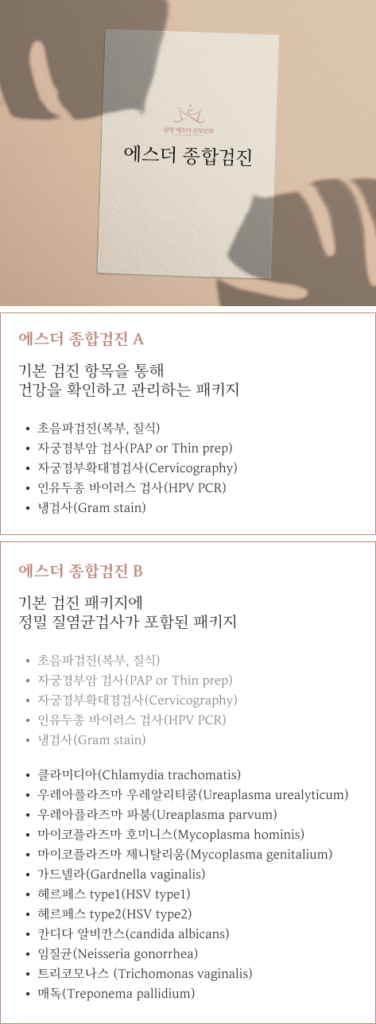

특별한 증상은 없지만, 정기적인 여성 검진을 원하시는 분,

검진의 필요성은 알지만, 어떤 검사를 해야 할지 판단이 어려우신 분,

최근 1년 동안 산부인과에 내원한 적이 없는 분,

공단 검진, 직장 검진 등을 했으나 구체적인 검사 결과 설명이나 상담에 부족함을 느끼는 분